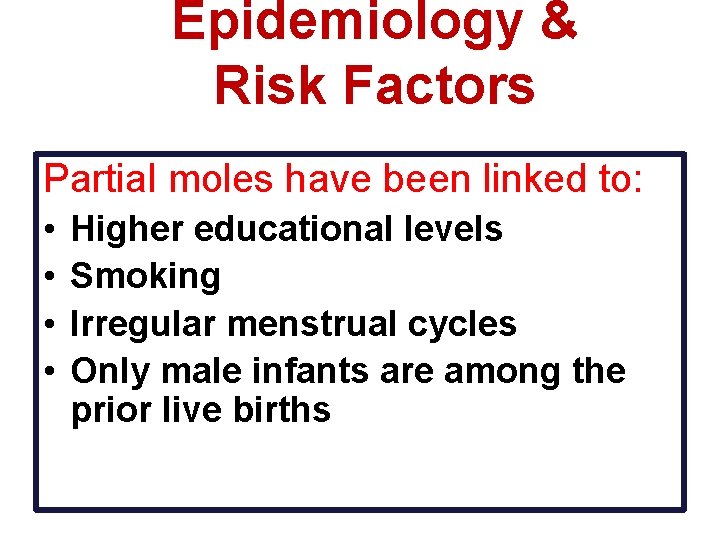

Epidemiology & Risk Factors Partial moles have been linked to: • • Higher educational levels Smoking Irregular menstrual cycles Only male infants are among the prior live births